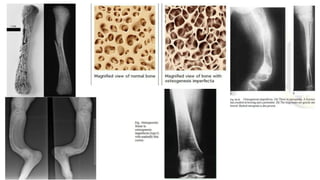

This document discusses a disease and its investigation and management. It begins by introducing Dr. Aniket Wankhede from MGIMS Sevagram and asks what the disease is. It then asks how the disease happens and discusses its causes. Next it asks how the disease appears on x-rays and describes symptoms some people experience living with it. Finally, it asks how the disease will be investigated and managed.